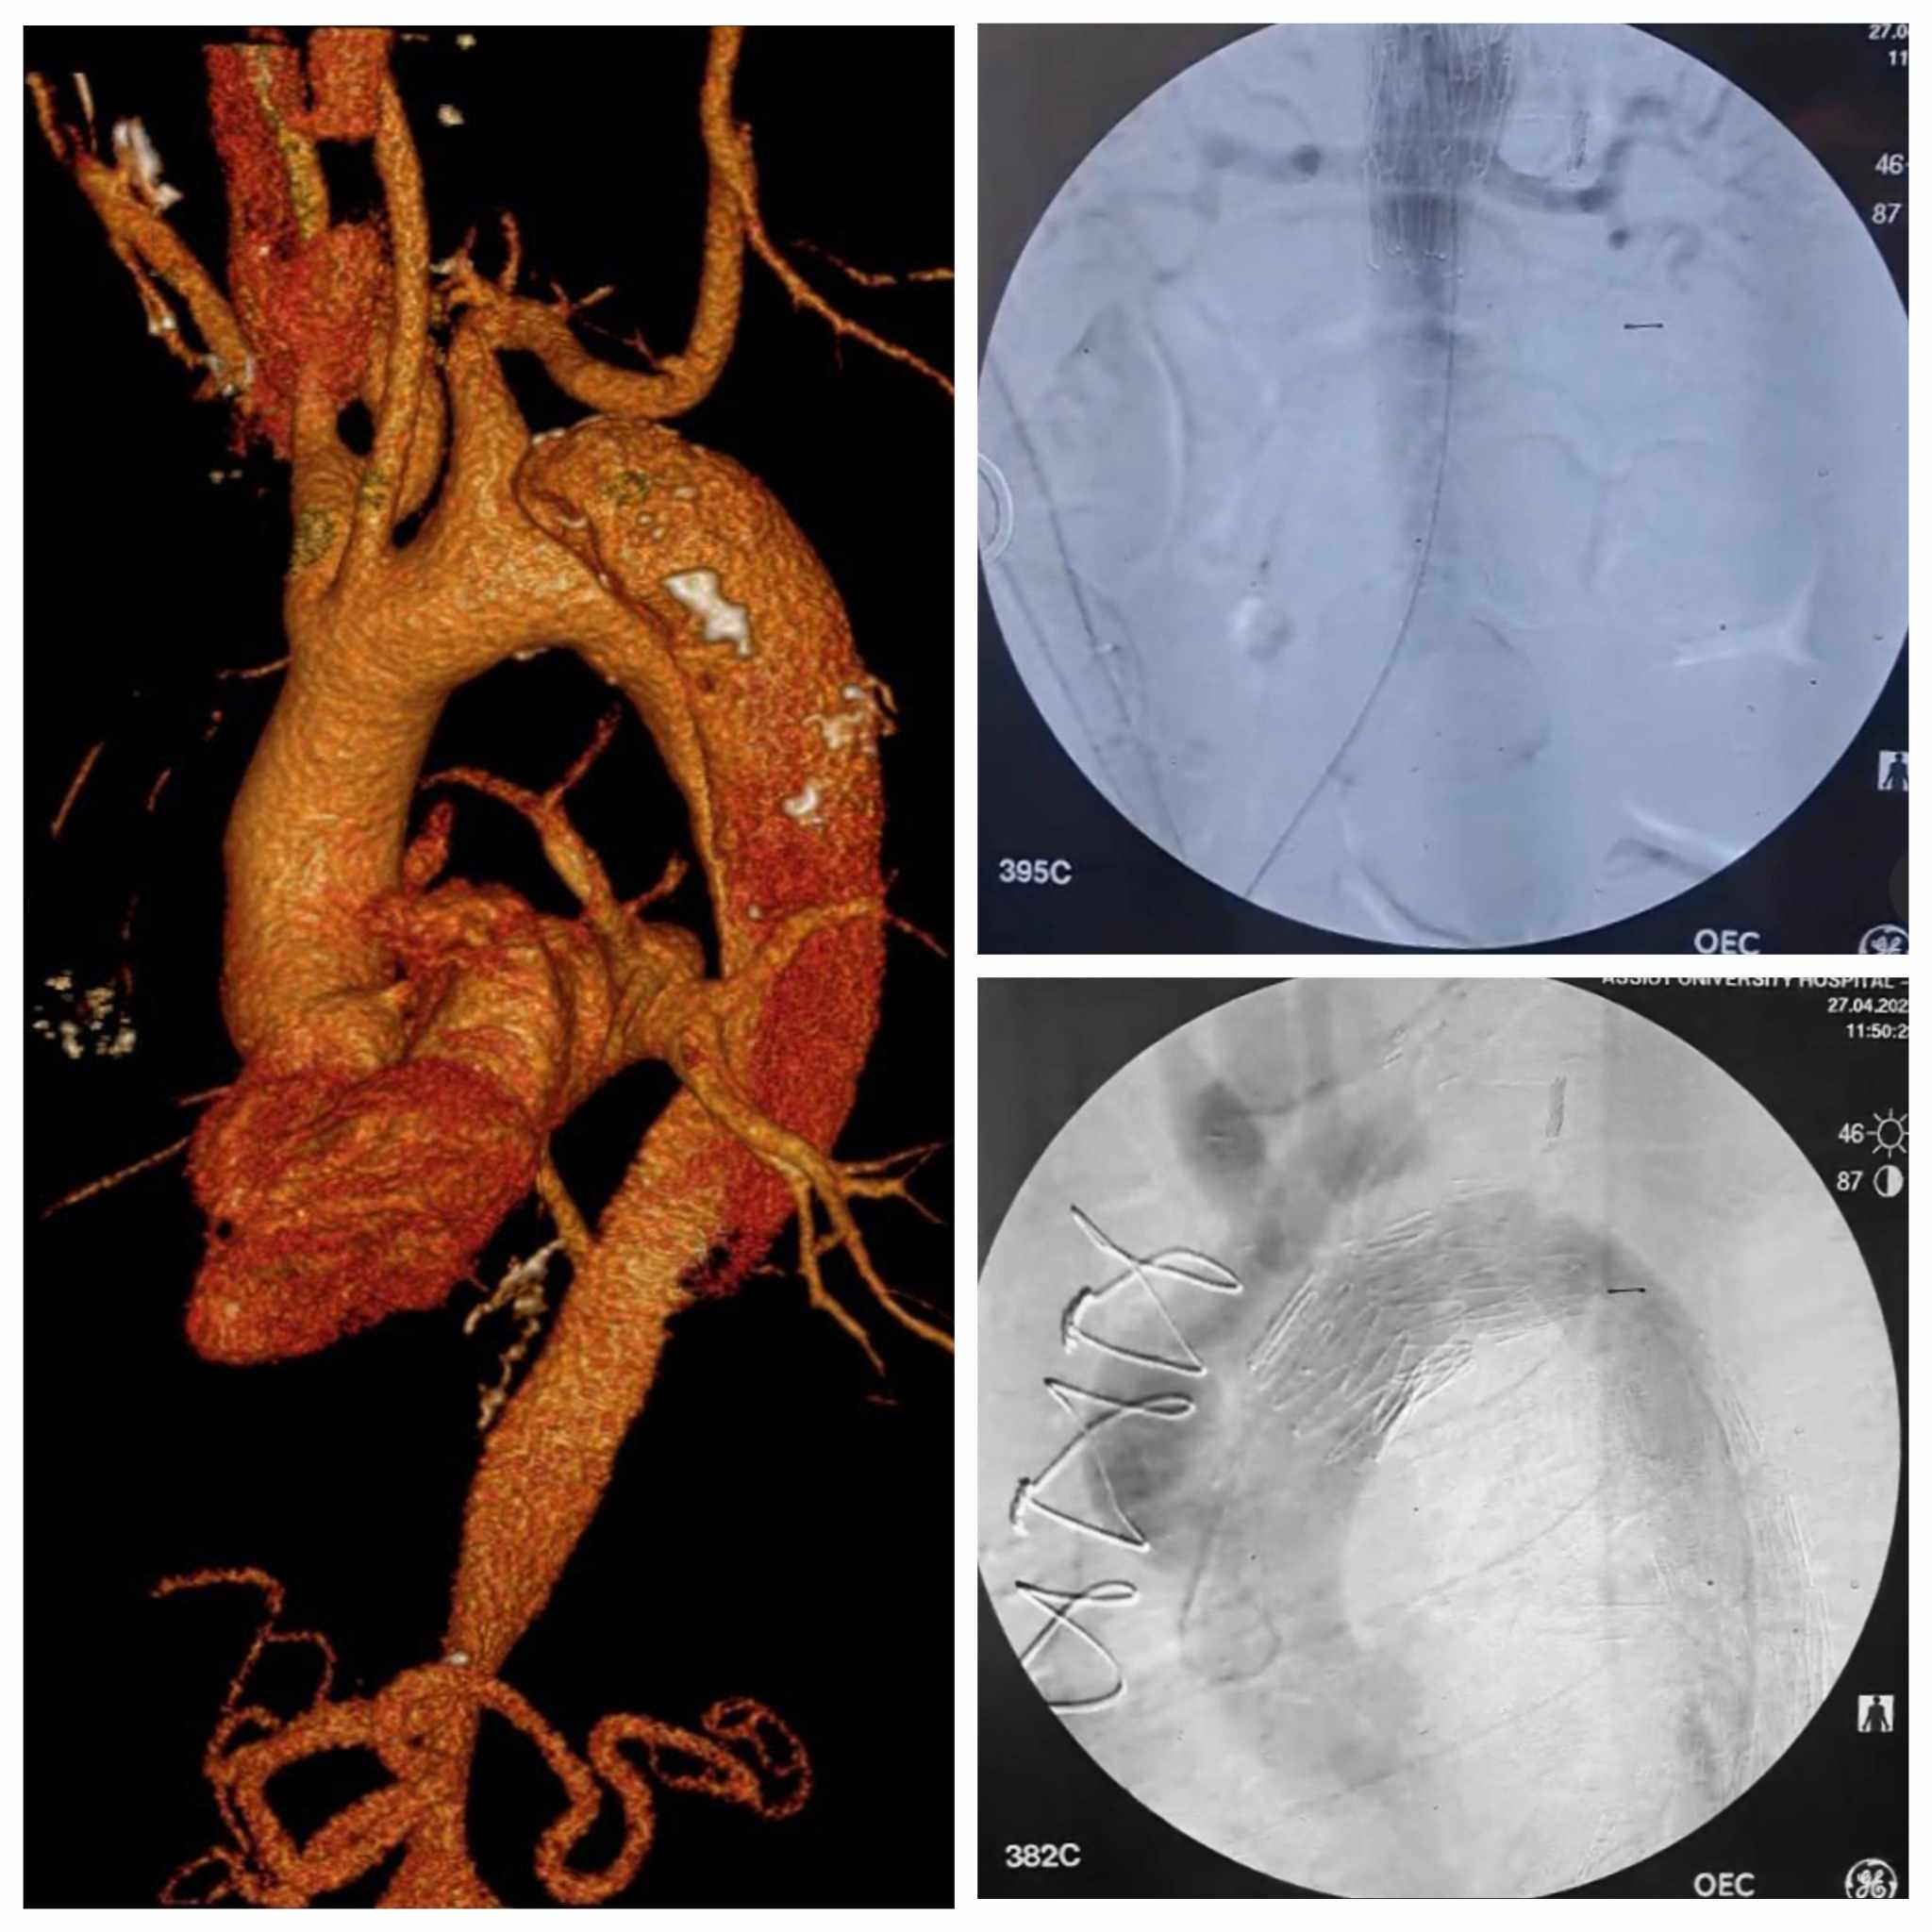

استكمالا للنجاحات التي تحققها مستشفيات جامعة أسيوط في مجال إجراء العمليات الجراحية الدقيقة، تحت رعاية الأستاذ الدكتور أحمد المنشاوي رئيس الجامعة، والأستاذ الدكتور علاء عطية عميد كلية الطب ورئيس مجلس إدارة المستشفيات الجامعية، نجح فريق طبي بقسم جراحة الأوعية الدموية بالتعاون مع فريق طبي بمستشفى القلب، في إجراء تدخل جراحي لحالة نادرة لمريض يعاني من انشطار بالشريان الأورطي.

كانت مستشفيات جامعة أسيوط قد استقبلت مريض يبلغ من العمر ٦٠ عاما، يعاني من انشطار بالشريان الأورطي من النوع (ب) مع تجمع دموي ممتد إلى الشرايين المغذية للمخ، وهي حالة عالية الخطورة، ليقوم الفريق الطبي بإجرائها على مرحلتين، حيث تضمنت المرحلة الأولى التدخل الجراحي، حيث تم التنسيق مع مستشفى القلب تحت إشراف الأستاذ الدكتور محمد عياد مدير المستشفى، وتم تشكيل فريق طبى برئاسة الأستاذ الدكتور هيثم علي حسن، أستاذ ورئيس قسم جراحة الأوعية الدموية، والدكتور أحمد إبراهيم، مدرس جراحة القلب والصدر، وضم كل من، الطبيب عمرو محمد ممدوح، مدرس مساعد بقسم جراحة القلب و الصدر، والطبيب محمد هشام القاضى، مدرس مساعد بقسم جراحة الأوعية الدموية، والطبيب عبدالرحمن شوقي الطوخى، مدرس مساعد بقسم جراحة الأوعية الدموية.

وأجرى الفريق الطبي عملية جراحية استمرت لمده ٤ ساعات، حيث قاموا بإعادة توصيل فروع الشريان الأورطي جراحياً باستخدام وصلات شريانية صناعية إلى شرايين المخ وشرايين الطرفيين العلويين، وقد وفرت هذه الخطوة منطقة هبوط آمنة ودعمت استمرار التروية للمخ والطرفيين العلويين، وهو ما كان ضروريا قبل الانتقال للمرحلة الثانية.

بينما تضمنت المرحلة الثانية استخدام القسطرة التداخلية بعد تخطيطا دقيقا وتنسيقا وثيقا بين التخصصات المختلفة، حيث قام الفريق الطبي بقسم جراحة الأوعية الدموية بالمستشفى الجامعى الرئيسى تحت إشراف الأستاذ الدكتور خالد عبد العزيز مدير المستشفى، وبرئاسة الأستاذ الدكتور هيثم علي حسن رئيس القسم، وضم كل من، الأستاذ الدكتور محمود إسماعيل، أستاذ جراحة الأوعية الدموية، والطبيب أحمد نجيب، مدرس مساعد بالقسم، بإجراء إصلاح للإنشطار بالشريان الأورطي الصدري والبطني باستخدام القسطرة التداخلية وتركيب دعامات مغطاة باستخدام تقنية (TEVAR).

وعقب ذلك قامت الأستاذة الدكتورة سلمى طه، أستاذ مساعد بقسم القلب، باستخدام تقنية التحفيز البطيني السريع من خلال تركيب منظم ضربات قلب مؤقت بالبطين الأيمن، والذى ساهم في تقليل حركة جدار الشريان الأورطي لزرع الدعامة المغطاة بالشريان الأورطي بدقة.